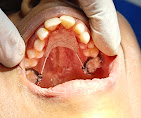

• Dental Implants & Full Mouth Implants: Permanent solutions for missing teeth, including advanced Zygomatic Implants for patients with bone loss.

• Jaw Bone Fracture Management: Specialized care for oral trauma and maxillofacial injuries.